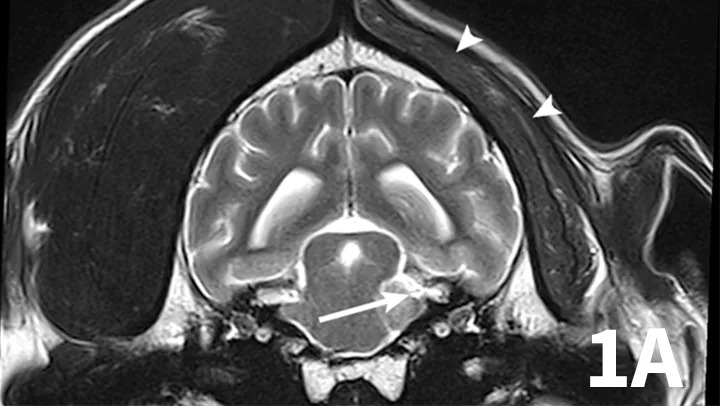

Nerve sheath tumors (NSTs) are perhaps the most common cause of chronic, progressive peripheral cranial nerve disease in older dogs. They arise from Schwann cells or pericytes, are typically slow growing, and are invasive to surrounding nervous system tissue. Metastasis is a rare event associated with NSTs. Whereas they most commonly affect the brachial plexus and lumbosacral plexus, NSTs also can arise within cranial nerves, with the trigeminal nerve most frequently affected. Clinical signs of trigeminal NSTs are ipsilateral to the NST and include unilateral masticatory muscle atrophy, facial hypalgesia, reduced corneal sensation, and Horner syndrome.1 Magnetic resonance imaging (MRI) is the modality of choice for identifying lesions. On MRI, NSTs are mass-like, tubular structures that are contiguous with a nerve (Figure 1).2 Lesions are often hyperintense (bright) on T2-weighted images (T2WIs), indicating high water content from edema, neoplastic cells, or inflammation, and strongly contrast enhance on T1-weighted images (T1WIs) following the delivery of gadolinium, suggesting a blood–nerve barrier breakdown or neoangiogenesis.

Transverse T2WI (A) and postcontrast T1WI (B) from a 10-year-old golden retriever with a 6-month history of left masticatory muscle atrophy. Adjacent to the left lateral pons is a mass-like lesion (arrow) confluent with the left trigeminal nerve that is T2-hyperintense and contrast-enhances on T1WI. There is profound atrophy of the left temporalis muscle (arrowheads), which is likewise T2-hyperintense with subtle contrast enhancement on T1WI. These findings are consistent with a nerve sheath tumor of the proximal trigeminal nerve with secondary neurogenic muscle atrophy.